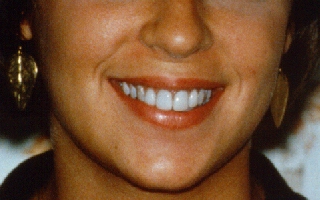

Porcelain Laminates

To Cover Tetracycline Stain

Here is another example of tetracycline

staining. The technique used for this patient is called porcelain

laminates. In this technique, a small amount (.5mm) of tooth structure

is removed from the front of the teeth and then an impression is taken

and sent to a laboratory. In the lab, space-age porcelain materials are

formed into a very thin piece called a laminate veneer. This porcelain

can be formed and colored to appear incredibly tooth-like. The

laminates are then tried on the tooth and are glued into place with

special bonding materials. An opaquing substance is mixed with the

bonding material to mask the dark gray shade of the underlying tooth. | |